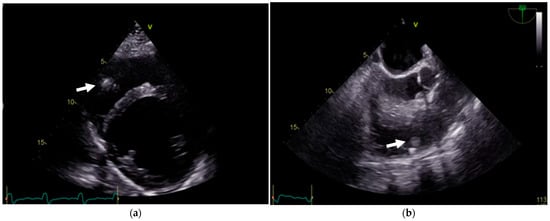

A TTE examination revealed a left ventricular (LV) end-diastolic dimension of 59 mm, a left ventricular end-systolic dimension of 49 mm, and a biplane LVEF of 25%. LV filling pressure was normal. The left atrium volume indexed was 41 mL/m2. Mild secondary mitral regurgitation was observed. The right ventricle (RV) had a basal dimension of 38 mm, and the tricuspid annular plane systolic excursion was 19 mm. The right atrium volume indexed was 28 mL/m2, with mild secondary tricuspid regurgitation. The estimated systolic pulmonary artery pressure was 37 mm Hg. A mobile vegetation approximately 10 mm in size was detected, attached to the ICD lead in the right ventricle. At TEE, another two additional vegetations attached to the ICD lead were identified (Figure 4).

Figure 4. (a) TTE showing a mobile vegetation (arrows) attached to the ICD lead in the right ventricle. (b) TEE confirming two additional vegetations attached to the ICD lead.